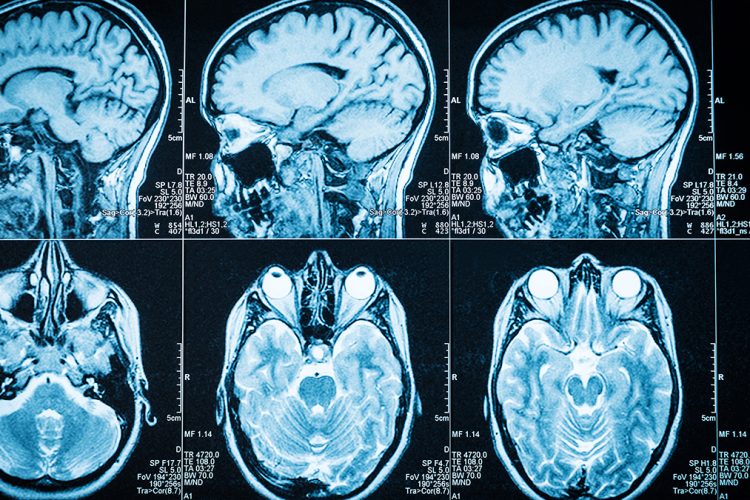

Simptoma kryesore për shumicën e njerëzve me epilepsi janë konvulsionet, që shkaktohen nga rritja e aktivitetit elektrik në tru.